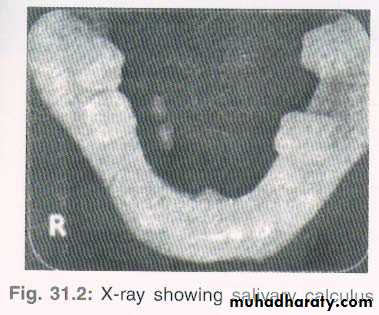

• Calculus